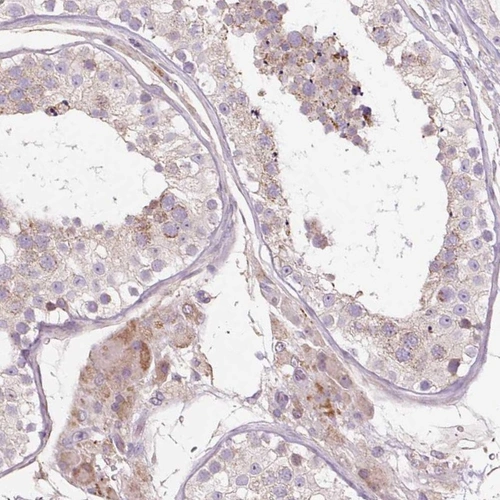

Immunohistochemical staining of human testis shows cytoplasmic positivity in cells in seminiferous ducts and Leydig cells.